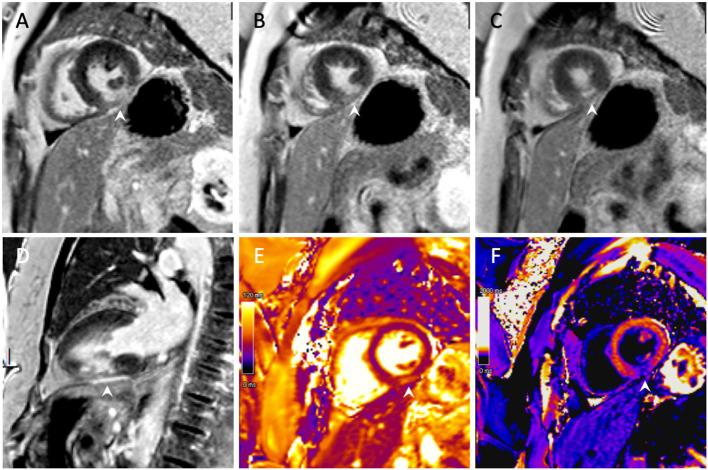

We report the first case of spontaneous coronary artery dissection (SCAD) potentially associated with scuba diving in a 65-year-old female with no medical history or known cardiovascular risk factors. She presented with sudden-onset chest pain during her descent whilst scuba diving on holiday. An initial ECG revealed transient abnormalities, but due to normal initial blood tests, a reassuring echocardiogram, and the resolution of her symptoms, she was discharged from hospital without a clear diagnosis. During her subsequent presentation to our hospital 1 week later, electrocardiographic evidence of an inferior myocardial infarction (MI) was noted, with an echocardiogram revealing regional wall motion abnormalities of the left ventricular inferior wall. Coronary angiography revealed the presence of a SCAD of the posterior left ventricular artery, with cardiac magnetic resonance imaging confirming the presence of an inferior MI. As recommended in the majority of cases of SCAD, this case was managed conservatively with a favorable clinical course.

我们报告了首例可能与潜水相关的自发性冠状动脉夹层(SCAD)病例,患者为一名65岁女性,无病史及已知心血管危险因素。她在度假潜水下降过程中突发胸痛。初始心电图显示短暂异常,但由于初始血液检查正常、超声心动图结果令人安心且症状缓解,她未明确诊断就出院了。1周后她再次就诊于我院时,心电图显示下壁心肌梗死(MI),超声心动图显示左心室下壁节段性室壁运动异常。冠状动脉造影显示左心室后动脉存在SCAD,心脏磁共振成像证实存在下壁MI。如同大多数SCAD病例所推荐的,该病例采取保守治疗,临床过程良好。